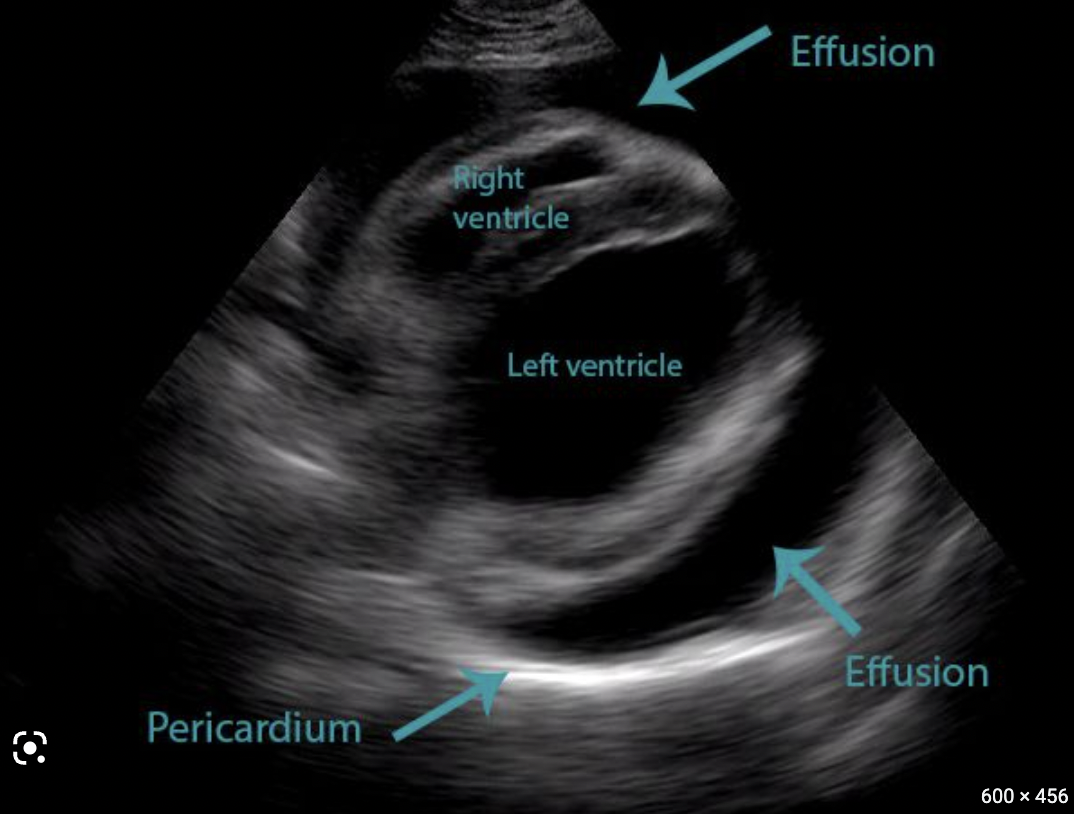

Imaging:

Transthoracic echocardiogram

• Check for pericardial effusion

Pericardial effusion

Cardiac tamponade